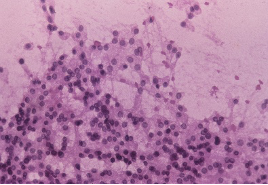

CYTOPATHOLOGY

Figs 1 and 2 from a mass in the right hypochondriac region.

Make your diagnosis.

Fig 1 : Giemsa x 100

Fig 2 : Giemsa x 400